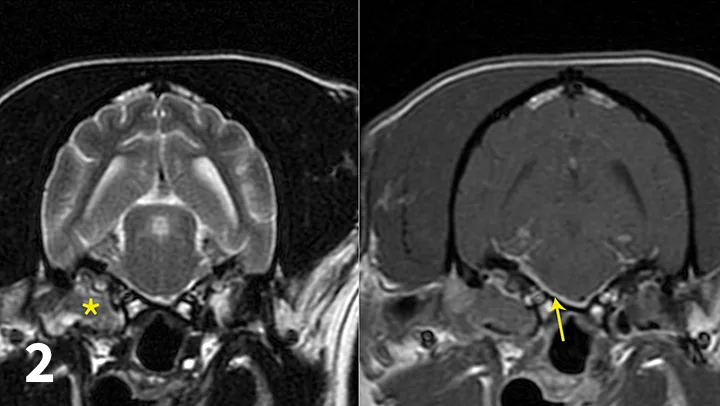

Contrast and post-contrast MRI images with markings denoting lesions in right middle ear extending into calvarium.

FIGURE 2

Transverse T2-weighted (left) and post-contrast T1-weighted (right) images obtained from a cockapoo with sudden onset of right peripheral vestibular dysfunction and right-sided facial paralysis. MRI showed right (*) worse than left middle ear disease with extension into the calvarium (otogenic meningitis; arrow) and into the right horizontal ear canal. Neutrophilic pleocytosis was present in the CSF (no bacteria seen on direct examination; CSF culture negative). The patient was treated with oral clindamycin for 1 month to reduce the intracranial portion of infection, and then right total ear canal ablation and lateral bulla osteotomy was performed. The histologic diagnosis for the tissue in the tympanic bulla was cholesteatoma, and bacterial culture identified secondary Staphylococcus pseudintermedius infection. The antibiotic was changed to amoxicillin-clavulanate based on antibiotic sensitivity testing.